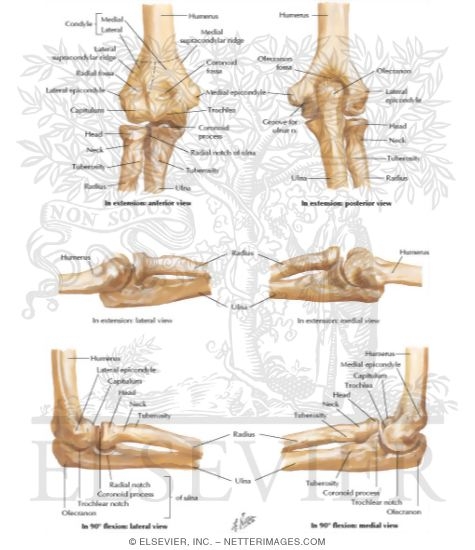

Bones of Elbow

Bones of Elbow